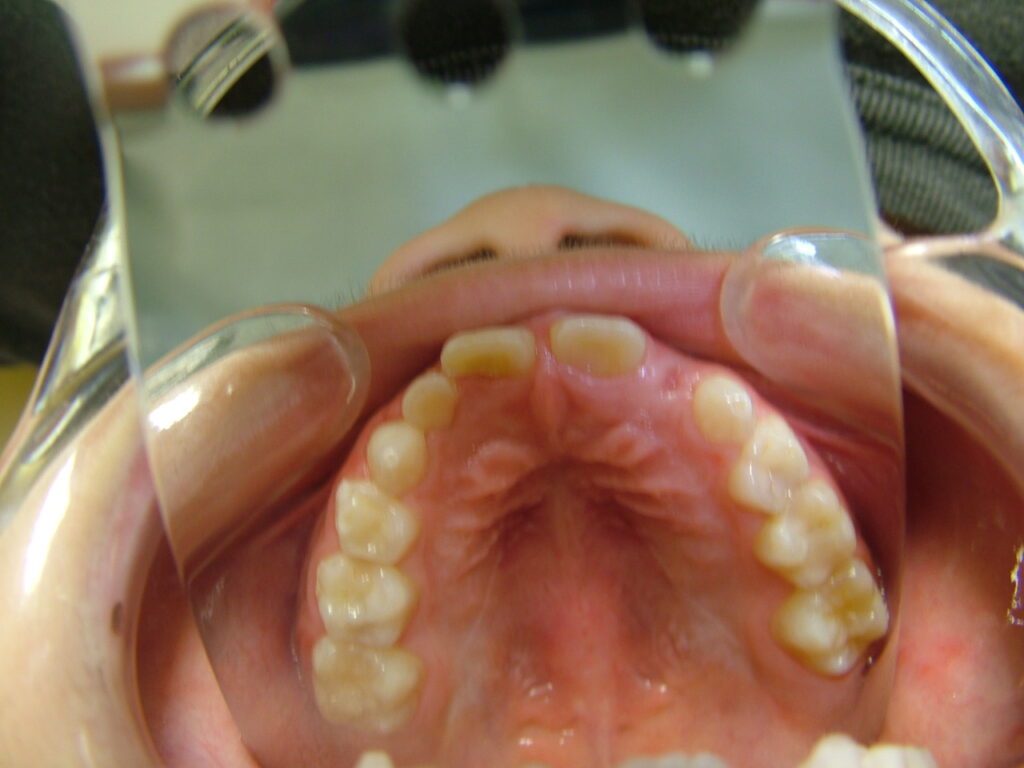

治療前

- 診断:1級咬合、左偏位、下永久歯(犬歯)萌出スペース不足

- 治療方針:非抜歯で行う。虫歯予防(フッ素)、歯磨き指導、舌位の改善、上下拡大床+補助断線→マウスピース矯正→下親知らずの抜歯、保定→メンテナンス